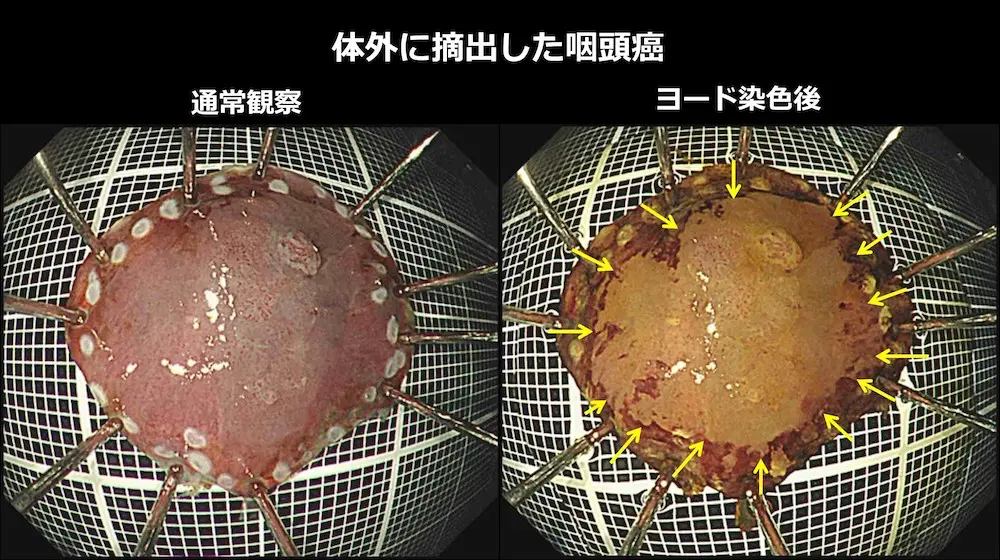

体外に摘出した咽頭癌をピンで張り付けて伸ばしています。

左(通常観察):白い点は、病変のすぐ外側に電気メスで付けたマークです。全周性にマークが認められ、切除予定だった範囲を切除できたことが分かります。

右(ヨード染色後):薬液(ヨード)で染色すると、黄色矢印内に色の違う部分が出てきます。この部分が咽頭癌です。病理検査(顕微鏡での分析)で咽頭癌は完全に切除されており、治癒と判定されました。